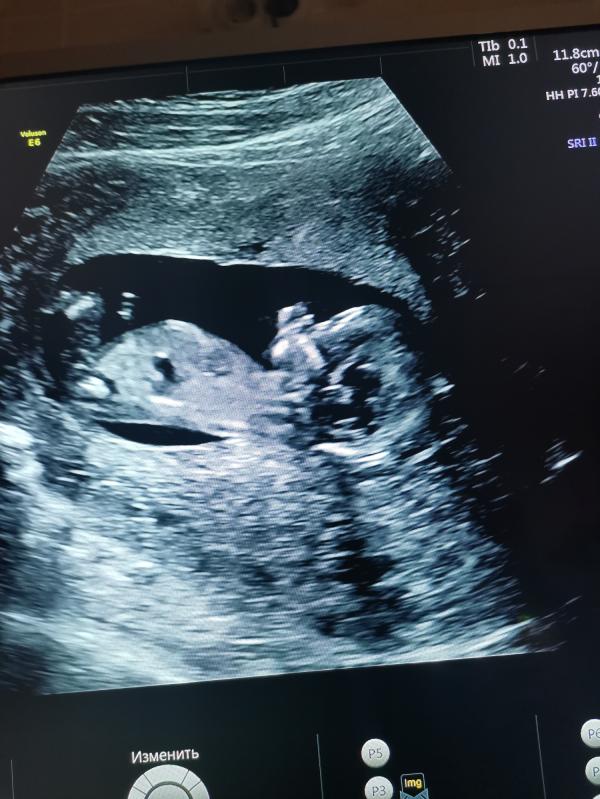

Оставлю это здесь на память 😀Наш первый скрининг, срок 12+6. Очень переживала по поводу этого дня. На УЗИ сказали всё хорошо, скорее всего девочка. Во время УЗИ подпрыгивает в животике, так радостно было на душе, мне кажется у меня улыбка до ушей была🤗